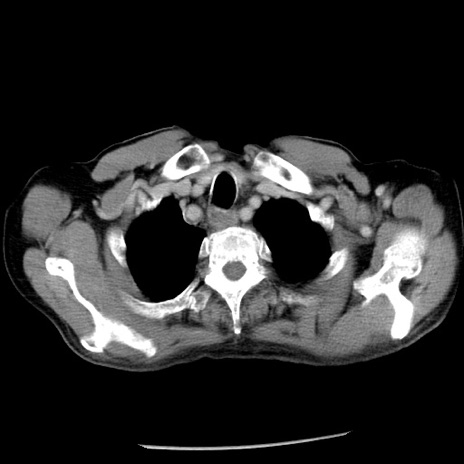

症例26(横断像)

【症例】80歳代男性

【主訴】嘔吐

【現病歴】昨晩2回嘔吐あり、今朝になっても嘔吐あり。来院。

【既往歴】胃潰瘍

【身体所見】意識清明、BT 37.6℃、BP 166/95mmHg、HR 100bpm、SpO2 97%、腹部:平坦・軟、腸蠕動音聴取良好、圧痛なし。

【データ】WBC 21900、CRP 1.46